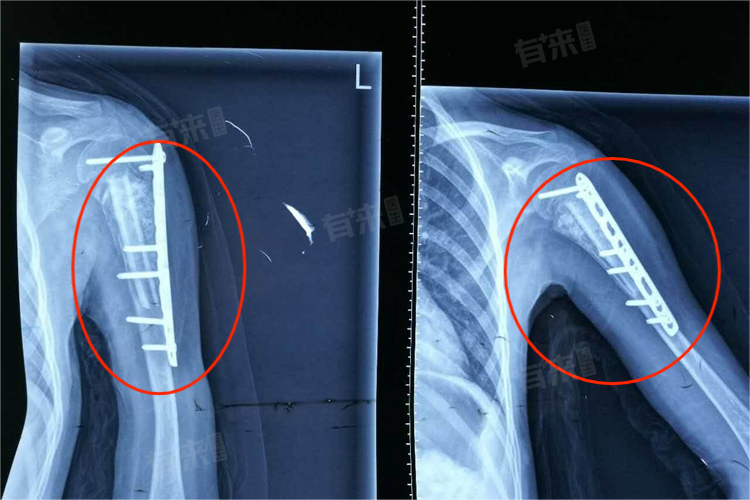

- 手术治疗:适用于骨折移位程度显著、对神经血管造成损伤或保守治疗无效的患者。手术治疗方法包括切开复位内固定术,即使用钢板、螺丝钉等内固定物将骨折部位复位并固定。对于儿童患者,还可以选择弹性髓内针固定等手术方式。